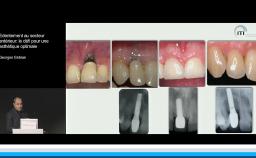

Cette conférence décrit la mise en œuvre d’un flux numérique dans le but de contribuer au respect des principes biologiques qui régissent le succès implant-prothétique. Le positionnement tridimensionnel du ou des implants est l’élément clé d’une bonne intégration tissulaire et esthétique. La possibilité d’anticiper ce positionnement lors d’une planification numérique par rapport aux tissus osseux, aux tissus mous et au projet prothétique est une plus-value importante. Autre avantage, la mise en charge et la temporisation immédiate sont plus ergonomiques. La technique est déclinée pour les édentements unitaires, pluraux, et complets.